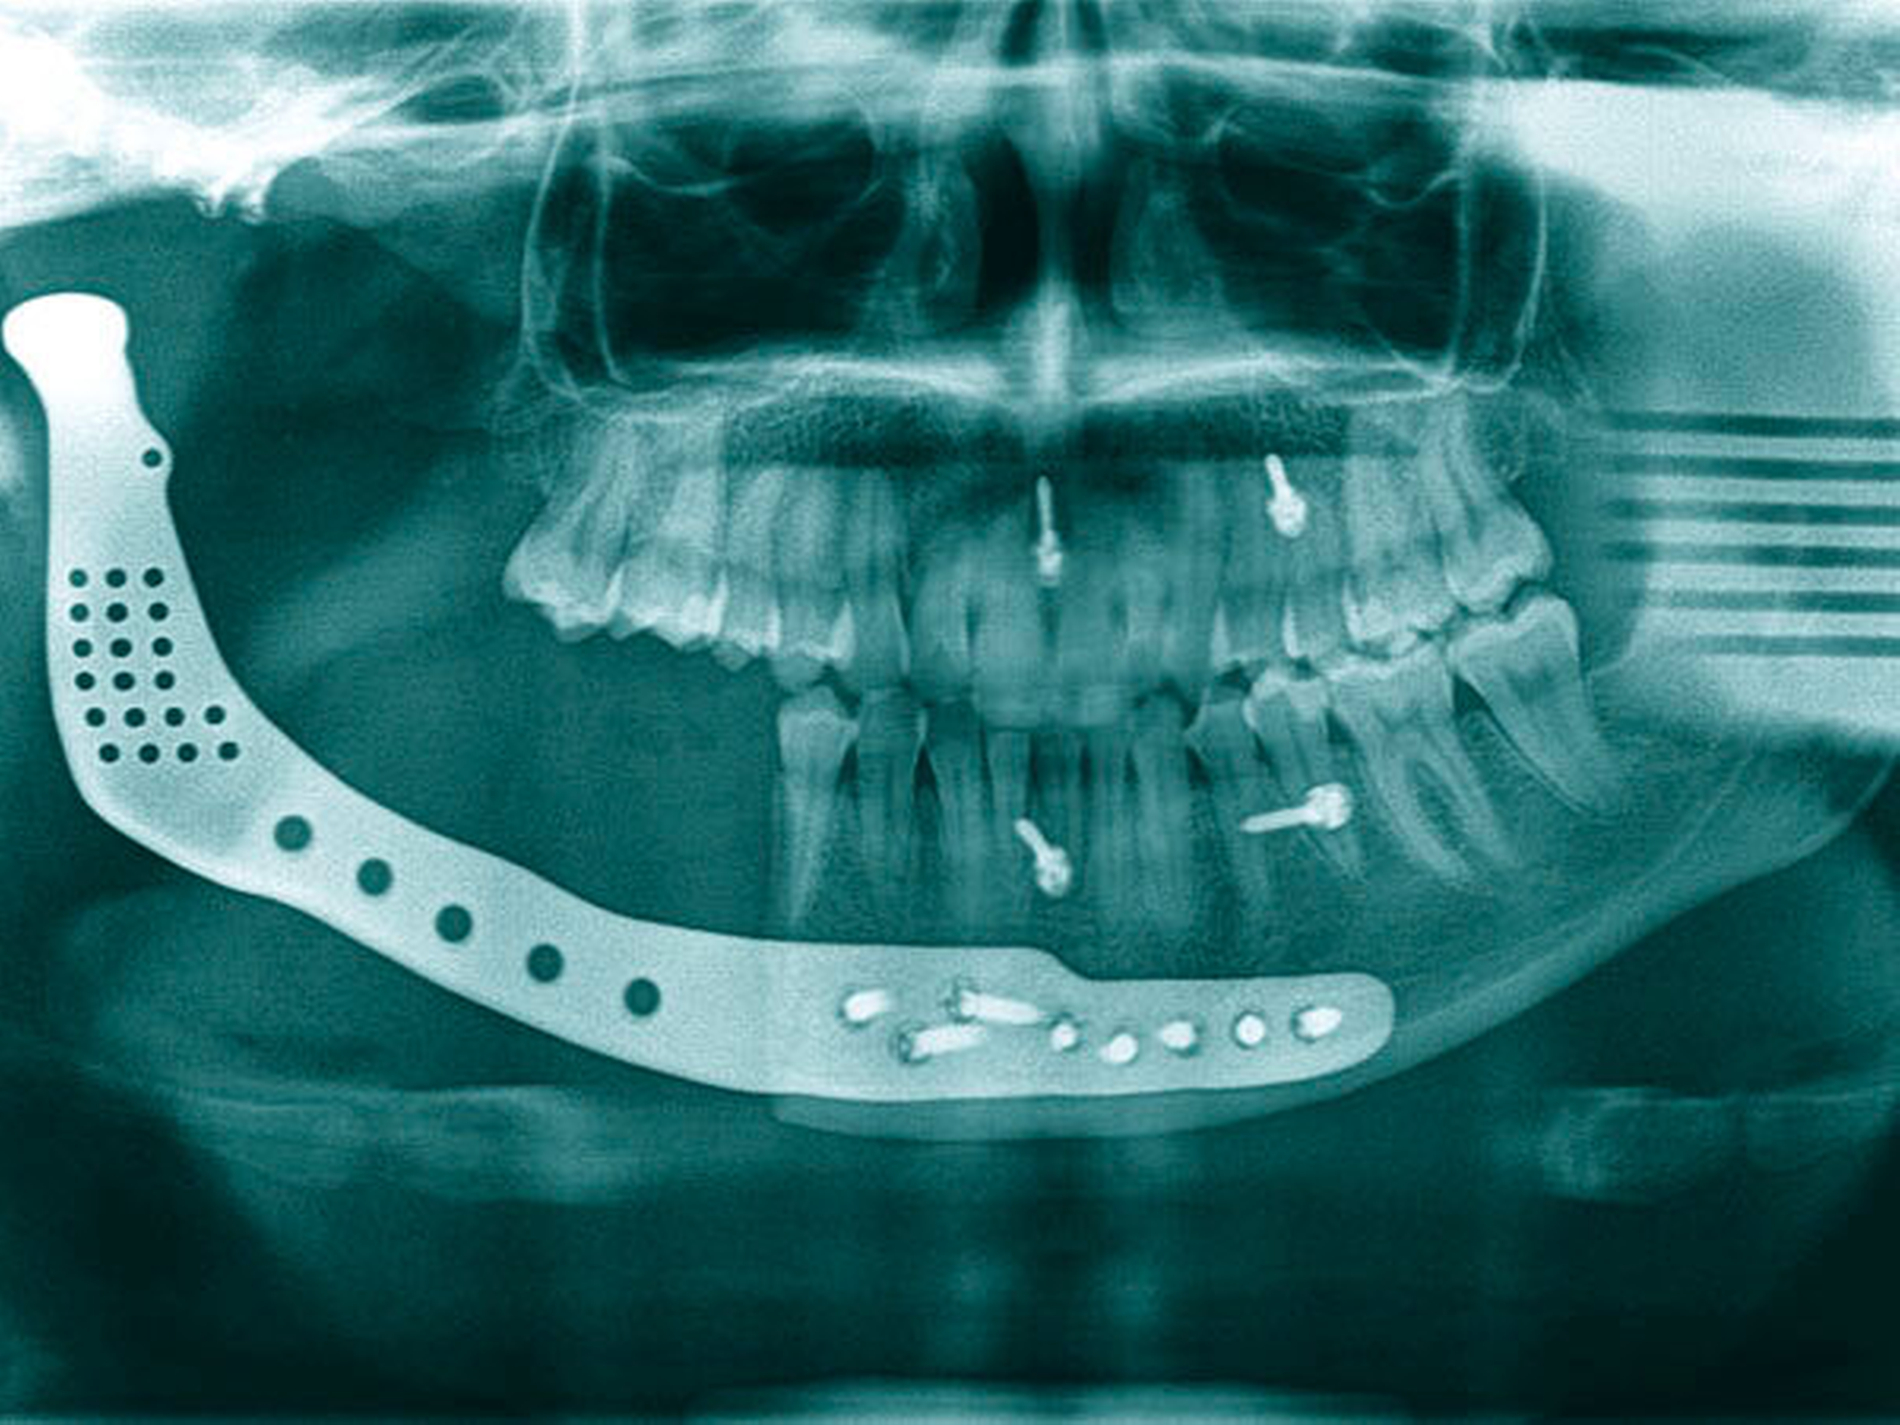

Dieser erfolgte nach Planung einer individuell angefertigten Gelenkprothese mit Resektion des rechten Rest-Caputs, des Collums und des Unterkiefers bis regio 44. Aus Gewichtsgründen wurde hier eine Titanlegierung verwendet und die Platte bis regio 34, 35 extendiert, um bei einer möglichen Progression der Osteomyelitis noch weitere Resektionsmöglichkeiten zu haben (Abbildung 9). Der Eingriff verlief komplikationslos und im weiteren postoperativen Verlauf berichtete die Patientin lediglich über Wärmesensationen und leichte Schwellungen.

Sollte es zu einer klinischen und radiologischen Remission kommen, wäre eine Rekonstruktion des Unterkiefers mit einem mikrovaskulär gestielten Beckenkammtransplantat möglich, dies wurde im individuellen Design der in situ befindlichen Platte entsprechend berücksichtigt.